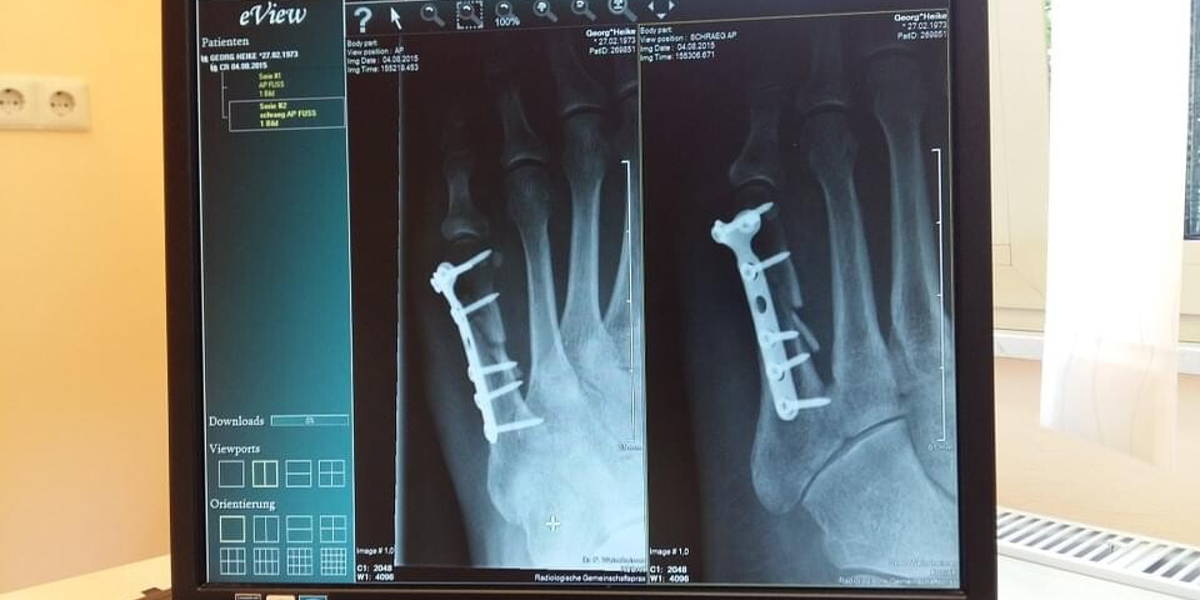

Wanneer elke minuut telt voor de patiënt, wil je als arts medische beelden direct kunnen raadplegen, ook als die in een ander ziekenhuis zijn gemaakt. Sinds deze maand realiseren het Radboudumc en CWZ deze ambitie: zij wisselen beelden digitaal uit via het zogeheten XDS-netwerk. Deze beveiligde verbinding maakt het mogelijk dat de twee verschillende elektronische patiëntendossiers (EPD’s) en beeldopslagsystemen van de Nijmeegse ziekenhuizen met elkaar communiceren.

De uitwisseling van digitale beelden vindt in eerste instantie plaats tussen de afdelingen neurologie en neurochirurgie, maar zal later dit jaar ook voor andere specialismen beschikbaar komen. Beelden als CT-scans zijn nu direct te zien voor collega’s in het andere ziekenhuis. DVD’s komen er niet meer aan te pas. “Nu winnen we kostbare tijd,” vertellen de betrokken neurologen Wim Mulleners (CWZ) en Ewoud van Dijk (Radboudumc). Zij spreken over een geweldige stap voorwaarts. “Deze stap is goed voor onze patiënten en zorgt bovendien voor veel gebruiksgemak.” In april maakte het Maxima Medisch Centrum bekend dat zij met drie andere ziekenhuizen in Zuidoost-Brabant ook via een beveiligd netwerk digitale beelden ging uitwisselen.